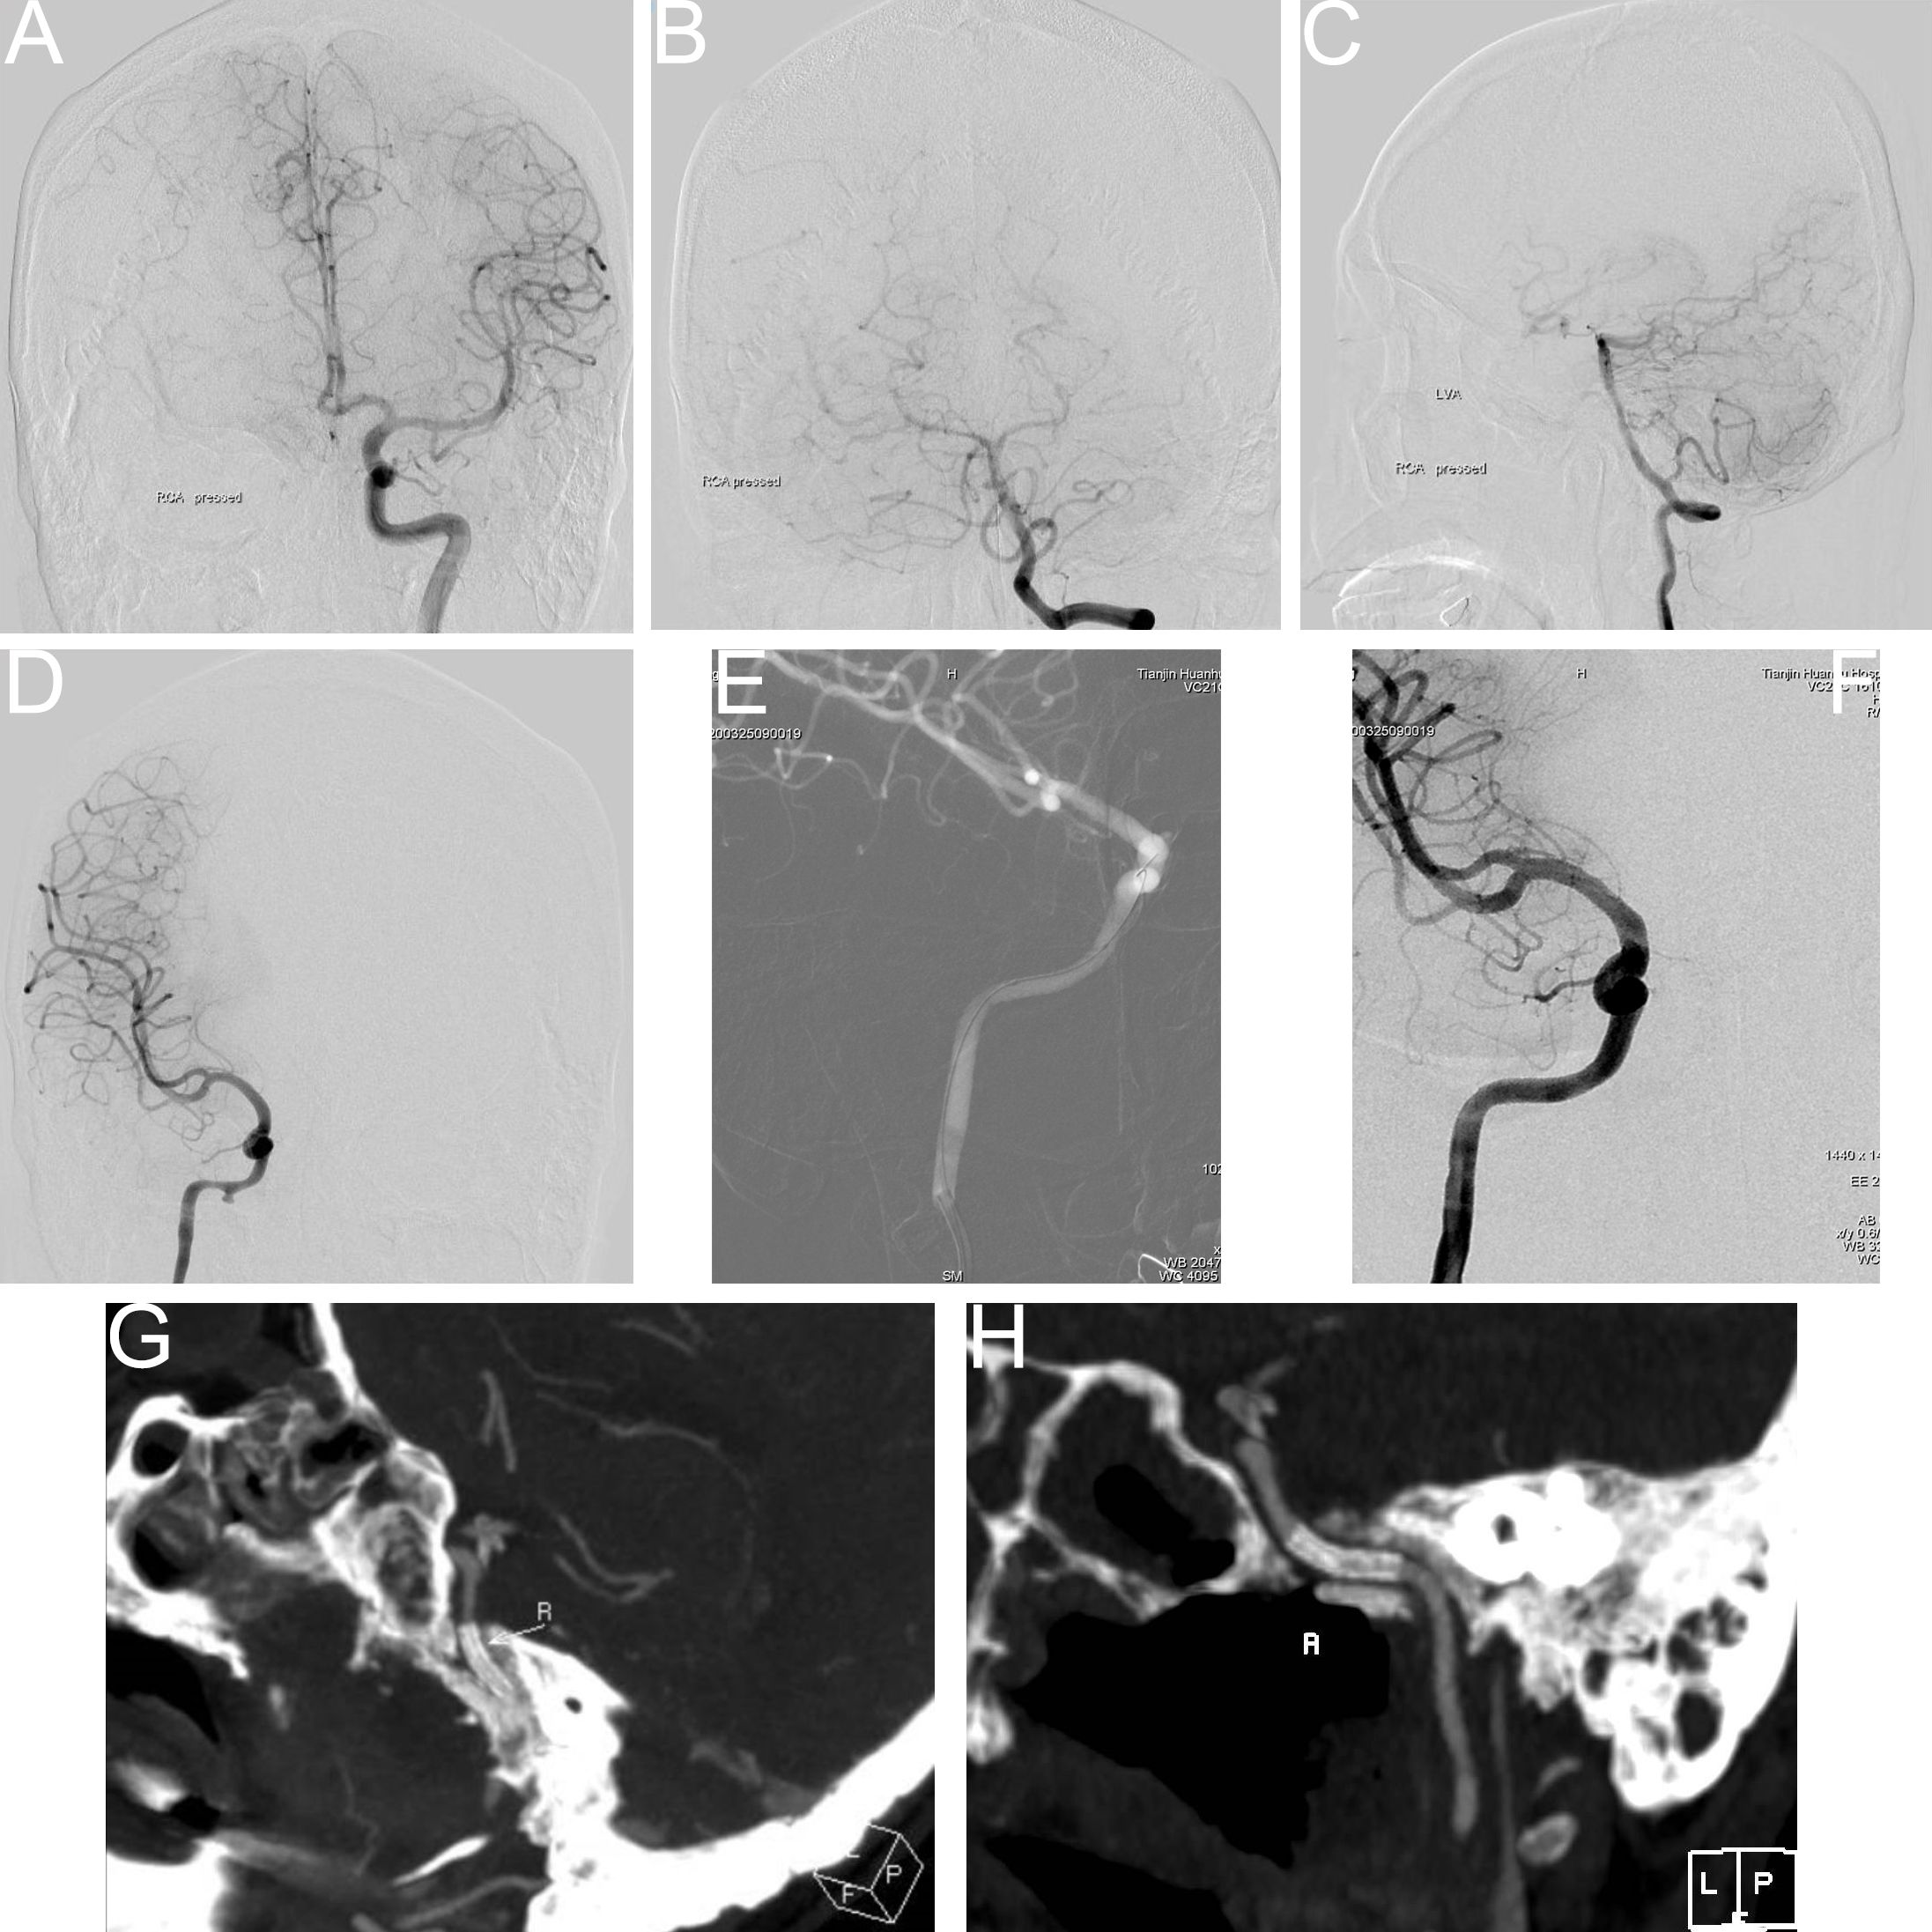

Figure 1

Balloon occlusion test (BOT) procedure steps. (A) Following balloon occlusion of the right internal carotid artery, insufficient compensatory blood flow was observed through the anterior communicating artery. (B) Balloon occlusion of the right internal carotid artery demonstrated limited compensatory blood flow through the posterior communicating artery. (C, D) Pseudoaneurysm identified at the ruptured segment of the right internal carotid artery (prior to stent implantation). (E) Intraoperative image during covered stent placement at the ruptured segment of the right internal carotid artery. (F) Post-stent implantation angiography showed unobstructed blood flow through the treated segment. (G, H) Computed tomography angiography (CTA) confirmed appropriate positioning of the covered stent.

During the procedure, the Matas test was first conducted (9). This involved manual compression of the affected side of the common carotid artery using the thumb from the contralateral side for several seconds prior to release. If the anterior and posterior communicating arteries were patent but demonstrated insufficient collateral perfusion, the balloon occlusion test (BOT) was generally deemed unnecessary. However, in cases where the anatomical course of the communicating arteries appeared adequate, BOT was performed for further assessment (Figure 1). If the BOT yielded negative results, a reduction test was carried out to objectively determine the feasibility of internal carotid artery occlusion (10, 11).

In cases with a positive BOT result, a Transend micro-slipper (Stryker, USA) was used to guide a Willis covered stent (Shanghai Minix Software Co., Ltd.) to the affected carotid artery segment harboring the aneurysm. The procedure was concluded if post-deployment cerebral angiography confirmed the disappearance of the aneurysm, satisfactory morphology of the carotid artery segment, and adequate visualization of intracranial branches. In cases where the aneurysm remained visible or recurrence was noted upon follow-up, intracranial–extracranial vascular bypass with aneurysm isolation surgery was performed (12, 13). This typically involved an anastomosis between the external carotid artery (or the lacerum segment of the ICA on the affected side) and the middle cerebral artery using a radial artery graft.

Upon admission, routine blood analysis indicated a hemoglobin level of 11.2 g/dL, raising suspicion of ICA rupture-associated hemorrhage. An urgent DSA examination confirmed the presence of a pseudoaneurysm in the petrous segment of the right ICA, with tumor-associated stenosis of the involved arterial segment. A subsequent BOT yielded a positive result (refer to Figures 3A, B).

Figure 3

(A, B) Digital subtraction angiography (DSA) indicated a pseudoaneurysm in the petrous segment of the right internal carotid artery, with tumor-related narrowing; the balloon occlusion test was positive. (C, D) Post–covered stent implantation DSA showed disappearance of the pseudoaneurysm, restoration of normal vascular morphology, and adequate perfusion of intracranial branch arteries. (E, F) Vascular reconstruction after stent implantation confirmed favorable vascular morphology and intracranial branch perfusion. (G, H) Follow-up DSA indicated recurrence of a small aneurysm distal to the stent in the petrous segment (C2) of the right internal carotid artery. (I) Vascular reconstruction angiography at three months post-stent implantation demonstrated a dissecting aneurysm.

Covered stent implantation was performed at the petrous segment of the right ICA, leading to the disappearance of the pseudoaneurysm. Post-procedural imaging demonstrated satisfactory vascular morphology and adequate perfusion of all intracranial branch arteries (refer to Figures 3C–F). Immunotherapy with sintilimab, a programmed cell death protein 1 (PD-1) immune checkpoint inhibitor, was administered every three weeks.

However, severe nasal bleeding recurred three months later. DSA and vascular reconstruction revealed septal luminal irregularities in the left carotid artery, consistent with a dissecting aneurysm (refer to Figures 3G–I).

A subsequent surgical procedure was undertaken, involving the creation of a vascular anastomosis from the right external carotid artery to the middle cerebral artery using a grafted radial artery. Concurrently, the cavernous and petrous segments of the right ICA were isolated. Immediate postoperative angiography confirmed patency of the bypass, with sufficient perfusion to the right middle cerebral artery and collateral supply to the ophthalmic artery. No perfusion was observed in the cervical, petrous, and cavernous segments of the right ICA (refer to Figures 4A, B).